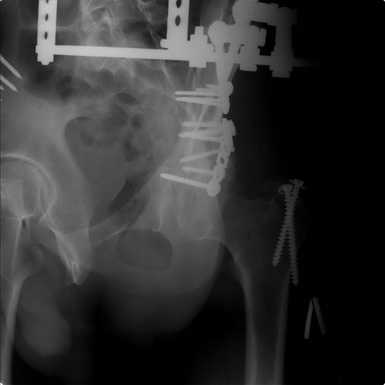

Добрый вечер, уважаемые коллеги. Прошу прощение за долгое молчание( компьютер был в долгосрочном ремонте). Больного с 9-ти месячной травмой таза мы прооперировали. Оценив свои возможности и совместив с вашими рекомендациями и советами (большое спасибо Рункову!), пошли задне-наружным доступом, с отсечением большого вертела. Закрепились 2-мя пластинками. Сверху закрепили аппаратом( передней рамой). На область перелома самого гребня повздошной кости не вмешивались. Снимки высылаю. Жду ваших отзывов и комментариев. Всем большое спасибо за активное участие в лечении больного. С ув.Андрей

Внутренняя фиксация получилась достаточно стабильная.А передняя рама наложена с целью дополнительной фиксации для нейтрализации мышц прикрепляющихся к крылу подвздошной кости, и исключить возможное расшатывание и возникнование нестабильности внутрених фиксаторов( уж очень большая нагрузка на эти 2 пластины).На открытом этапе операции мобилизовали только часть линии всего перелома( около 1/4 части начиная от свода и проксимально), а остальная часть находится в рубце и патологическая подвижность в ней есть хоть и не выражена) А о ранней нагрузке никто и не думал. А как на ваш взгляд, в какие сроки в такой ситуации разрешить полную нагрузку? Я считаю, что только при сращении перелома, подвержденные лучше бы КТ